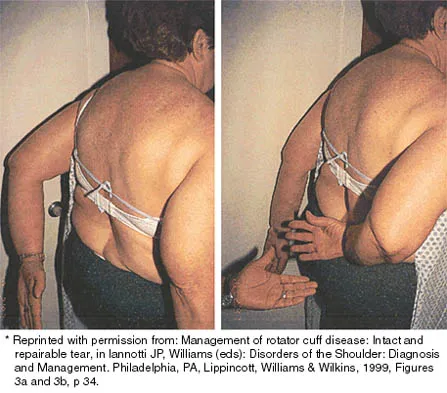

While lifting weights, a patient feels a pop in his arm. He has the deformity shown in Figure 30. If left untreated, the patient will have the greatest deficiency in